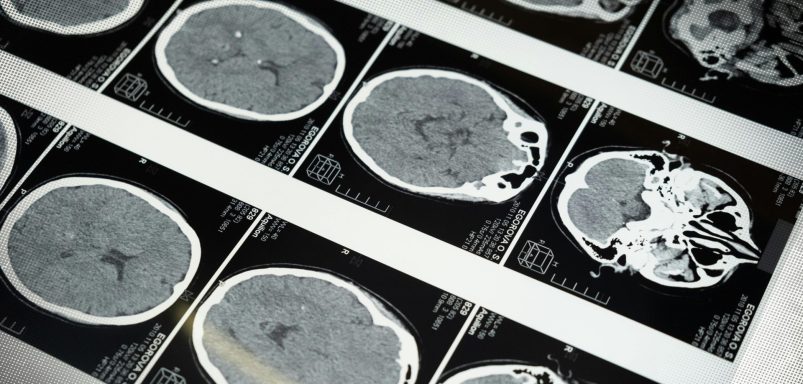

What goes on in the brain of a dying person?